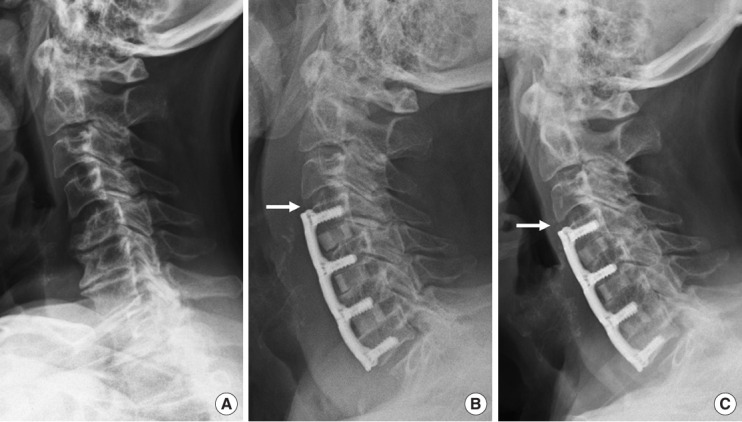

目的:探讨颈椎前路椎间盘切除术融合(ACDF)后邻接层骨化发展(ALOD)的相关因素及相关临床结果。方法:我们回顾性回顾了140例因退行性椎间盘疾病而行原发性ACDF的成年人的记录。我们比较ACDF后有和没有ALOD的患者。术前和至少24个月随访时评估影像学测量和与ALOD相关的因素。临床结果包括临床邻接节段病变(CASP)的发生率、翻修手术和患者报告的结果。结果:与颅侧和尾侧ALOD相关的因素是板到椎间盘距离短(PDD),相邻节段后凸,前凸性ACDF引起的连接节段后凸,以及术前前纵韧带骨化(OALL)。颅ALOD组的平均最终邻接节段运动范围(ROM)(6.9°±2.8°)小于无ALOD组(12°±4.2°)(p < 0.01)。尾侧ALOD组的平均最终邻接段ROM(5.5°±2.4º)也低于无尾侧ALOD组(8.2º±3.7º)(p < 0.01)。与无ALOD的患者相比,尾部ALOD患者的casp手术发生率更高(p = 0.02),而颅侧ALOD患者的casp手术发生率无差异(p = 0.69)。结论:与ALOD相关的因素是与ACDF相邻的后凸节段,前凸融合,术前OALL和短PDD。ALOD与较小的节段性ROM相关,对于尾侧而非颅侧ALOD的患者,CASP翻修手术的发生率较高。

Results: Factors associated with both cranial and caudal ALOD were short plate-to-disc distance (PDD), adjacent-segment kyphosis, hyperlordotic ACDF causing junctional segment kyphosis, and preoperative ossification of the anterior longitudinal ligament (OALL). Mean final adjacent-segment range of motion (ROM) was less in those with cranial ALOD (6.9° ± 2.8°) than in those without cranial ALOD (12° ± 4.2°) (p < 0.01). Mean final adjacent-segment ROM was also less in those with caudal ALOD (5.5° ± 2.4º) than in those without caudal ALOD (8.2º ± 3.7º) (p < 0.01). The incidence of CASP-required surgery was higher in those with caudal ALOD (p = 0.02) but no different in those with cranial ALOD (p = 0.69) compared with those without ALOD.

Conclusion: Factors associated with ALOD were a kyphotic segment adjacent to ACDF, hyperlordotic fusion, preoperative OALL, and short PDD. ALOD was associated with less segmental ROM and, for those with caudal but not cranial ALOD, higher incidence of revision surgery for CASP.